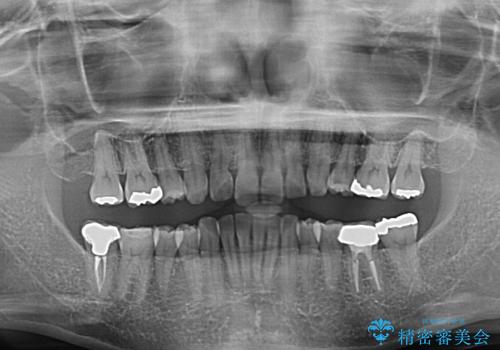

- 以前行った抜歯矯正が後戻りし、開いてしまったスペースが気になるとのことで来院された患者様です。

インビザラインを用いて開いてしまったスペースと前歯のデコボコを改善することとしました。

矯正治療後には気になっていた銀歯をセラミッククラウンやセラミックインレーにて治療することとしました。

上顎前歯を左右対称となるように歯列を整えたいとのことでしたが、すり減って形態が大きく異なっていたため、できる範囲での仕上がりとなりました。